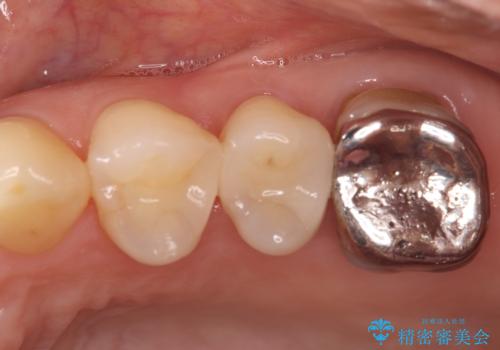

銀歯からセラミックへ。右上奥歯の精密根管治療と審美修復

担当医 河口智英